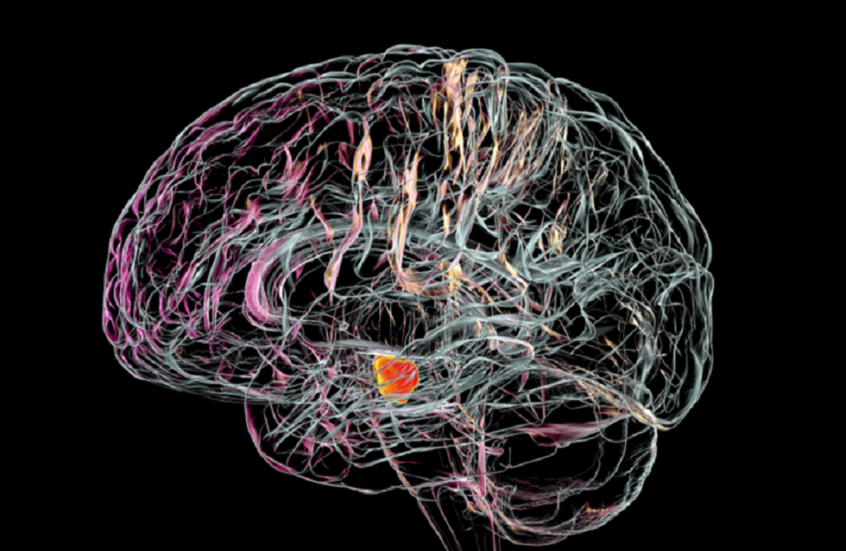

علاقة مقلقة بين نوع مياه الشرب وزيادة خطر مرض عصبي مزمن

أظهرت دراسة حديثة أن نوع مياه الشرب التي يتناولها الإنسان قد يكون له علاقة بزيادة خطر الإصابة بمرض باركنسون.

ويعرف مرض باركنسون بأنه اضطراب عصبي مزمن يسبب الرعاش وصعوبة في الحركة والتوازن وتيبس العضلات ومشاكل في الكلام، وتتفاقم أعراضه مع مرور الوقت.

وفي الدراسة، ركز باحثون من مدينة نيويورك وأريزونا على تحليل تأثير مصادر المياه الجوفية على هذا المرض.

ودرس الفريق أكثر من 12 ألف شخص مصاب بباركنسون، وأكثر من مليون شخص غير مصابين، جميعهم يعيشون بالقرب من مواقع أخذ عينات المياه الجوفية لمراقبة جودتها.

وأظهرت النتائج أن الأشخاص الذين يحصلون على مياههم من مواقع المياه الجوفية الحديثة — أي التي أُنشئت خلال الـ 75 عاما الماضية — كانوا أكثر عرضة بنسبة 11% للإصابة بالمرض مقارنة بمن يحصلون على المياه من المصادر القديمة. كما تبين أن شرب المياه من طبقات المياه الجوفية الكربوناتية، وهي طبقات صخرية قابلة للذوبان تحمل المياه، يزيد من خطر الإصابة بنسبة تصل إلى 62% مقارنة بالمياه من الطبقات الجليدية.

ويعتقد الخبراء أن المياه الجوفية القديمة أكثر نقاء لأنها تأتي من أعماق أكبر، ما يحميها من الملوثات مثل المعادن الثقيلة والمبيدات الحشرية.

وتنتشر طبقات المياه الجوفية بشكل واسع في الولايات المتحدة، حيث تخدم نحو 145 مليون شخص، ويأتي حوالي نصف مياه الشرب في البلاد من هذه المصادر. ويُعتقد أن طبقات المياه الجوفية الجليدية، التي تشكلت أثناء العصر الجليدي، تعمل كمرشح طبيعي بفضل تكوينها من الرمل والحصى، ما يقلل من تلوث المياه.

وأكدت بريتاني كرزيزانوفسكي، معدة الدراسة والباحثة في معهد أتريا للأبحاث في نيويورك، أن "إحدى طرق دراسة التعرض للتلوث الحديث هي من خلال مياه الشرب. المياه الجوفية الحديثة، الناتجة عن أمطار السبعين إلى الخمسة والسبعين عاما الماضية، تتعرض لمزيد من الملوثات، بينما المياه القديمة تبقى أنظف إذا كانت محمية بعمق. وجدت دراستنا أن عمر المياه الجوفية وموقعها يعدّان من عوامل الخطر البيئية المحتملة لمرض باركنسون".

ولفتت الدراسة إلى أن نحو 3463 من المصابين بمرض باركنسون يحصلون على مياه الشرب من طبقات المياه الجوفية الكربوناتية، و515 من طبقات المياه الجوفية الجليدية، و8329 من طبقات مياه جوفية أخرى. بينما بين غير المصابين، حصل 300264 على المياه الكربوناتية، و62917 على المياه الجليدية، و860993 على مصادر أخرى.

وحذر الباحثون من أن الدراسة لا تثبت أن المياه الحديثة تسبب باركنسون، لكنها تشير إلى وجود ارتباط محتمل بين نوع الماء وخطر الإصابة، خاصة عند التعرض الطويل للمياه الجوفية الحديثة والملوثة. ويُنصح بغلي المياه أو استخدام فلاتر منزلية للحد من الملوثات.